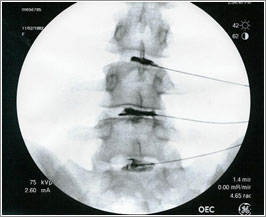

- Discogram(ÁÖ»ç½Ã¼ú)